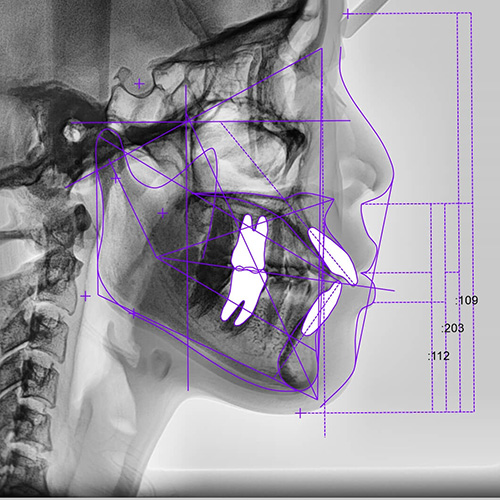

診断・治療計画立案

セファログラムのデータを元に、分析・診断をして、患者さまに適した治療計画を立案し、丁寧にご説明します。不明点などは遠慮なくお尋ねください。